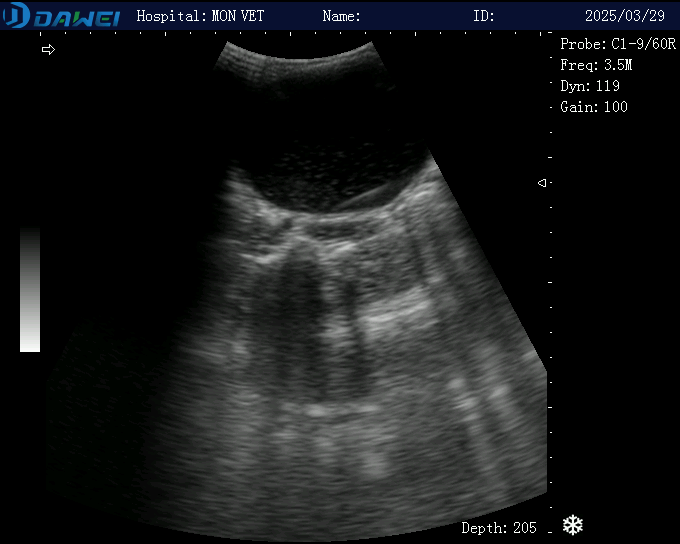

Hình ảnh siêu âm sỏi bàng quang tại phòng khám thú y MonVet- Cẩm Phả.

• Siêu âm: Xác định hình ảnh sỏi trong bàng quang.